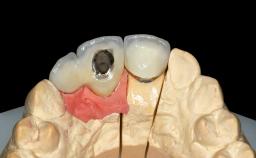

A 45-year-old woman was referred for management of an infection associated with two implant-supported crowns replacing the maxillary central incisors. Two tissue-level implants had been placed and restored with cemented single metal-ceramic crowns in those sites 4 years previously. The patient presented with a draining sinus (i.e. a pathological duct from an abscess cavity to a surface) 3 mm from the midfacial peri-implant mucosal margin of the maxillary right implant crown. She was in good general health, did not smoke, showed a good oral hygiene status, and had no history of periodontal disease. The implants were well positioned. While the patient was very satisfied with the appearance of her crowns, she had noted that the peri-implant soft tissue had receded since their insertion and was concerned about the possibility of further recession.